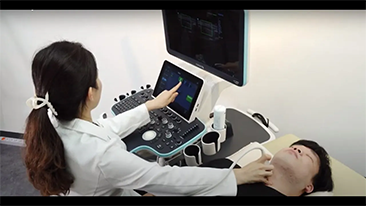

Resona 7

Nowe fale w innowacji ultrasonograficznej z technologi? Zone Intelligence

Od czasu kiedy zosta?a za?o?ona, Firma Mindray nieustannie poszukuje nowych sposob├│w na polepszenie precyzji w diagnostyce. Dzi?ki zastosowaniu najbardziej rewolucyjnej technologii ZONE Sonography? Technology, platforma ZST+ zastosowana w aparacie Resona 7 przenosi jako?? obrazu ultrasonograficznego na wy?szy poziom dzi?ki strefowemu uzyskiwaniu obrazu - zone acquisition i obr├│bkce danych kana?owych.

Oprócz uzyskiwania jako?ci obrazu typowego dla aparatów klasy premium, Resona 7 rozszerza mo?liwo?ci klinicznych badań USG dzi?ki rewolucyjnej funkcji V Flow, s?u??cej do oceny hemodynamiki naczyń, a tak?e najlepszej na rynku funkcji inteligentnego, automatycznego uzyskiwania p?aszczyzny na podstawie zestawów danych obj?to?ciowych 3D, umo?liwiaj?cej diagnozowanie stanu Centralnego Uk?adu Nerwowego u p?odu. Aparat Resona 7 ??czy w sobie najbardziej intuicyjn?, wielodotykow? obs?ug? za pomoc? gestów oraz wszystkie kluczowe funkcje kliniczne, co sprawia i? jest prawdziwym liderem we wprowadzaniu innowacji w ultrasonografii.